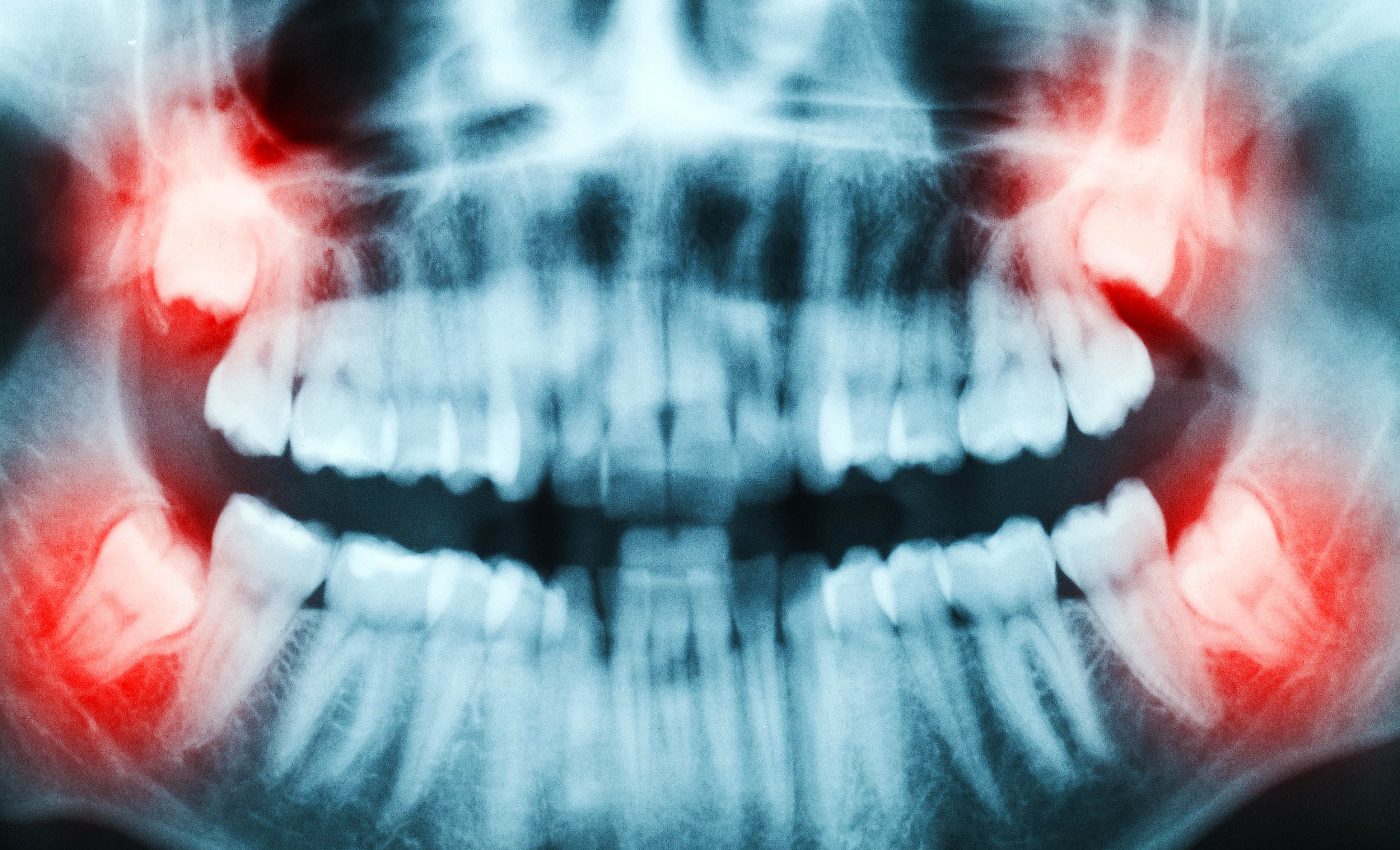

Millions of Americans schedule wisdom‑tooth surgery each year, treating the third molars as little more than biological clutter. However, these grinders hide valuable dental stem cells at their core, and may prove to be critical in the treatment of several serious diseases.

Roughly 10 million wisdom teeth are removed in the United States every year. Most head straight to a biomedical‑waste bin, yet each freshly extracted tooth offers a painless harvest of living tissue.